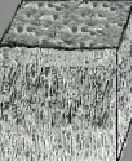

Ver fotografía derecha superior: Superficie de esmalte

vista con microscopio electrónico de barrido. |

| Esmalte

visto al microscopio electrónico de barrido |